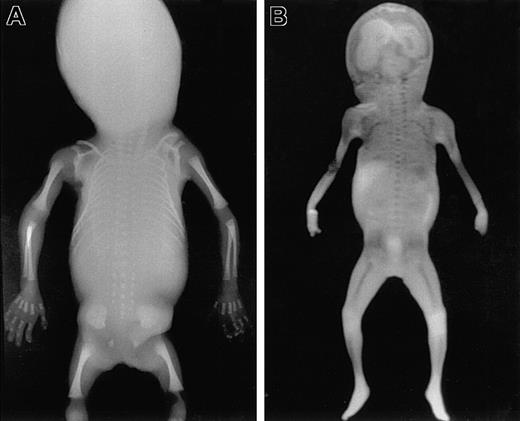

To identify areas of BM in the fetal skeleton, total body radiography of fetuses of different gestational ages was performed (Figure 1A) showing ossification centers in the skull, spine, claviculae, scapulae, costae, humeri, ulnae, radius, pelvis, femora, tibiae, fibula, and the bones of the hands and feet. Corresponding sites could be visualized using MRI (Figure 1B). All sites except the skull were confirmed to contain hematopoietic cells by microscopic histologic analysis (Figure2). In the skull, only the mandibula, maxilla, clivus (a bony surface in the posterior fossa), and occipital bones contained hematopoietic cells during the gestational ages studied. The other skull bones showed bone formation but no marrow containing hematopoietic cells and were therefore excluded from calculation of the BM compartment. The hematopoietic sites confirmed by histologic analysis correlated well with the BM areas found on the MRI (Figure 3), and thus the volume of these hematopoietic sites could be determined from the MRIs.

Total body radiography and coronal MRI.

Total body anteroposterior radiograph image (A) and T1-weighted coronal scout MRI (B) of a fetus 21 weeks of gestational age. Areas of ossification containing BM are clearly recognizable as radiodense structures in the radiograph. Corresponding areas of low signal intensity (dark) are visible in the MRI. These areas are well delineated from the surrounding cartilage, which shows much higher signal intensity (light).

To identify the BM hematopoietic sites in the fetus at different gestational ages, total body radiography was performed identifying ossification centers. Corresponding sites were made visible using MRI. The BM compartment could be measured reliably with MRI because differences in signal intensities between cartilage and BM provided the possibility to accurately discriminate these structures in the fetus. To verify that these areas were indeed hematopoietic sites, corresponding histologic sections were made of all these structures. Up to 22 weeks of gestation, hematopoietic cells were detected in all bones except the calvarial bones (skull). Only after 22 weeks of gestation a few hematopoietic cells could be detected in histologic sections, suggesting the beginning of hematopoiesis in the calvarial bones. The absence of hematopoietic cells in the calvarial bones can be explained by the fact that in the frontal and parietal skull bones osteogenesis does not develop from cartilage but takes place through intramembranous ossification. This apparently occurs later in development than enchondral ossification. The connective tissue in which intramembranous ossification occurs and the ossification centers containing the BM compartment in other bones were shown to have the same intensity using MRI. This initially suggested that all these bones belonged to the hematopoietic BM compartment. Based on the histologic analysis, however, the calvarial bones were excluded from addition to the BM compartment. All other bones including the other skull bones have enchondral osteogenesis22 and do develop from cartilage. In these bones cartilage could be easily distinguished from BM using MRI because of the different intensity.